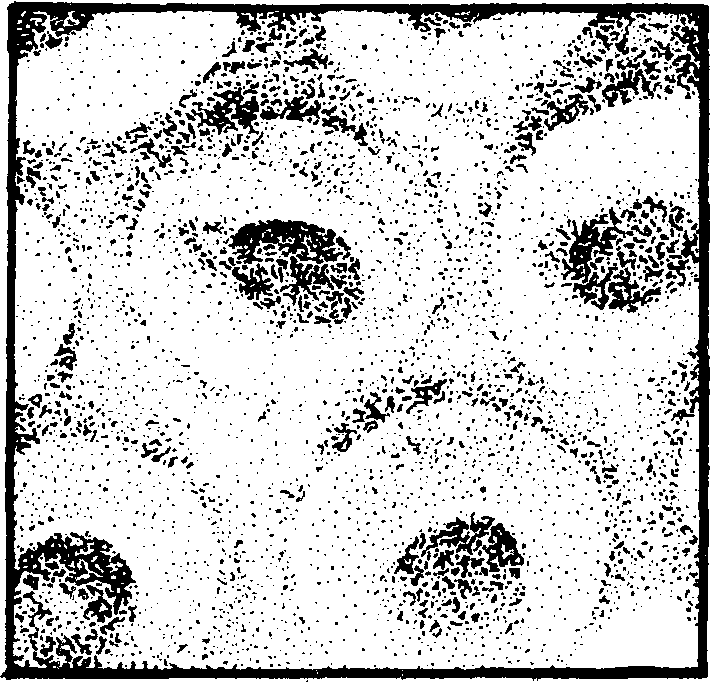

红细胞(简称RBC)是血细胞中最多的一种。成熟的红细胞呈双凹圆盘形(见图1.4-1),直径约为8微米,周边较厚,中心较薄,无细胞核。男性每立方毫米血液中红细胞数为450—550万个(平均500万个),女性约为380—460万个(平均420万个)。红细胞内含有红色的血红蛋白(简称Hb),因而血液呈红色。血红蛋白约占红细胞重量的32%。男性每100毫升血液中含有血红蛋白12—15克,女性含有11—13克。红细胞运输氧的能力是由其中的血红蛋白实现的。血红蛋白中的Fe2+能在肺内(氧分压高)与氧结合为氧合血红蛋白,在组织中(氧分压低)又将氧放出,成为还原血红蛋白。红细胞中的血红蛋白还有运输二氧化碳的能力。

图1.4-1 正常人的红细胞的立体形态(立体电子显微镜照相)